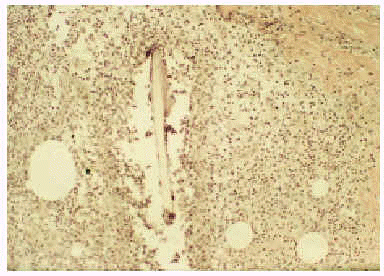

El estudio histopatológico de una de las lesiones mostró la presencia de una epidermis normal y un infiltrado granulomatoso de predominio perifolicular (fig. 2), constituido por linfocitos y polimorfonucleares con multitud de células gigantes de cuerpo extraño. Muchos de los folículos pilosos se encontraban destruidos (fig. 3). La tinción con PAS no evidenció la presencia de hongos. Mediante término de reacción en cadena de la polimerasa (PCR) se detectó ADN del virus varicela zóster (VVZ). Las lesiones involucionaron espontáneamente en aproximadamente 20 días, sin desarrollarse lesiones residuales.

Fig. 2.--Infiltrado granulomatoso perifolicular con linfocitos, polimorfonucleares y células gigantes a cuerpo extraño (hematoxilina-eosina, 40x).